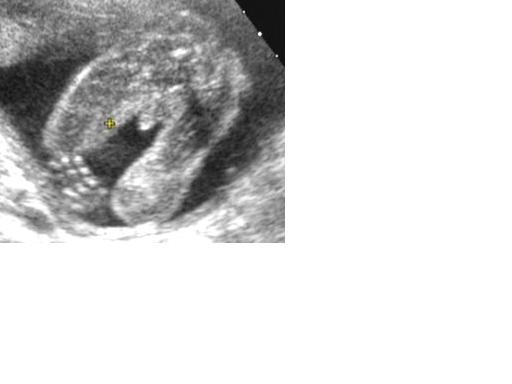

FIÚ LESZ!!!!!!!!!! Mindenki azt mondta, hogy kislány lesz, apukám is azt mindta, hogy olyan a hasam mint anyukámé (2 nővérem van). És már annyira biztos voltam én is, hogy lány ruhákat válogattam, mert kaptunk sok ruhát, hogy válogassunk belőle bátran. Fiút akartunk, úgyhogy most nagy az öröm! :lol: :lol: :lol:

Ifjabb Németh Károly a becsületes neve. :D

Mindene megvan, teljesen egészséges, és 492,9 grammos.

Kép Elég egyértelmű